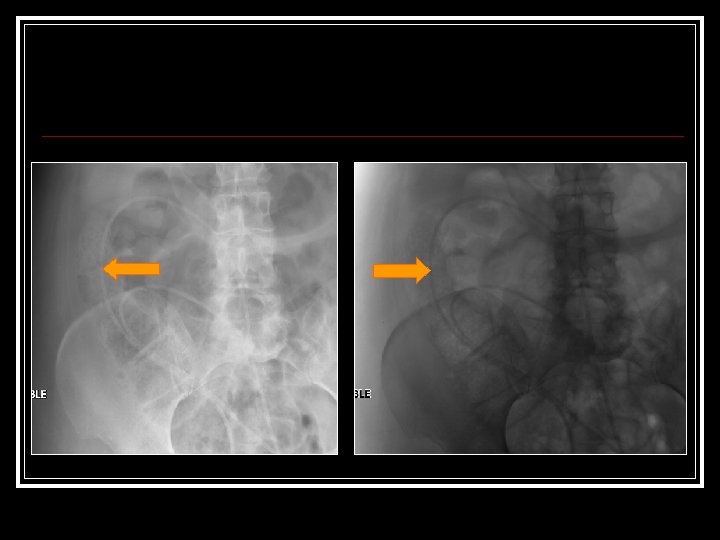

March 22 [cont’d] n n n Neuro. Surgery Consulted ? Shunt Malfxn Initial exam: Intub, withdrawing disconjugate gaze Drain off 20 cc via shunt reservoir Pt immediately awakes, begins reaching for ETT Cannot palpate distal shunt got AXR:

March 23 -26: Further 20 cc drained off [02: 00 am] n In a. m Cardiac cath: Normal Coronaries n Echo: Mild LV hypokinesis n Pt had shunt studies n went to OR third ventriculostomy n Pt does well. Discharged home n